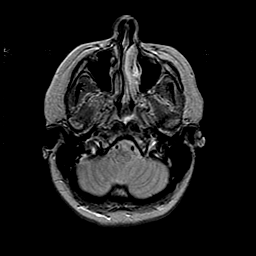

MR Study #2 -- Slice #10